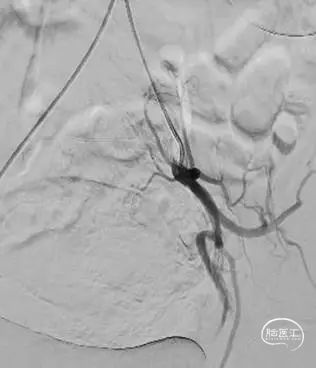

栓塞前

栓塞后

栓塞前

栓塞后